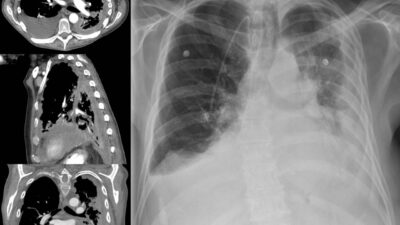

• You or a loved one must have been diagnosed with lung cancer.

• Your lung cancer was diagnosed pathologically via a method other than imaging (e.g., biopsy, cytology, fine needle aspiration, or lobectomy).